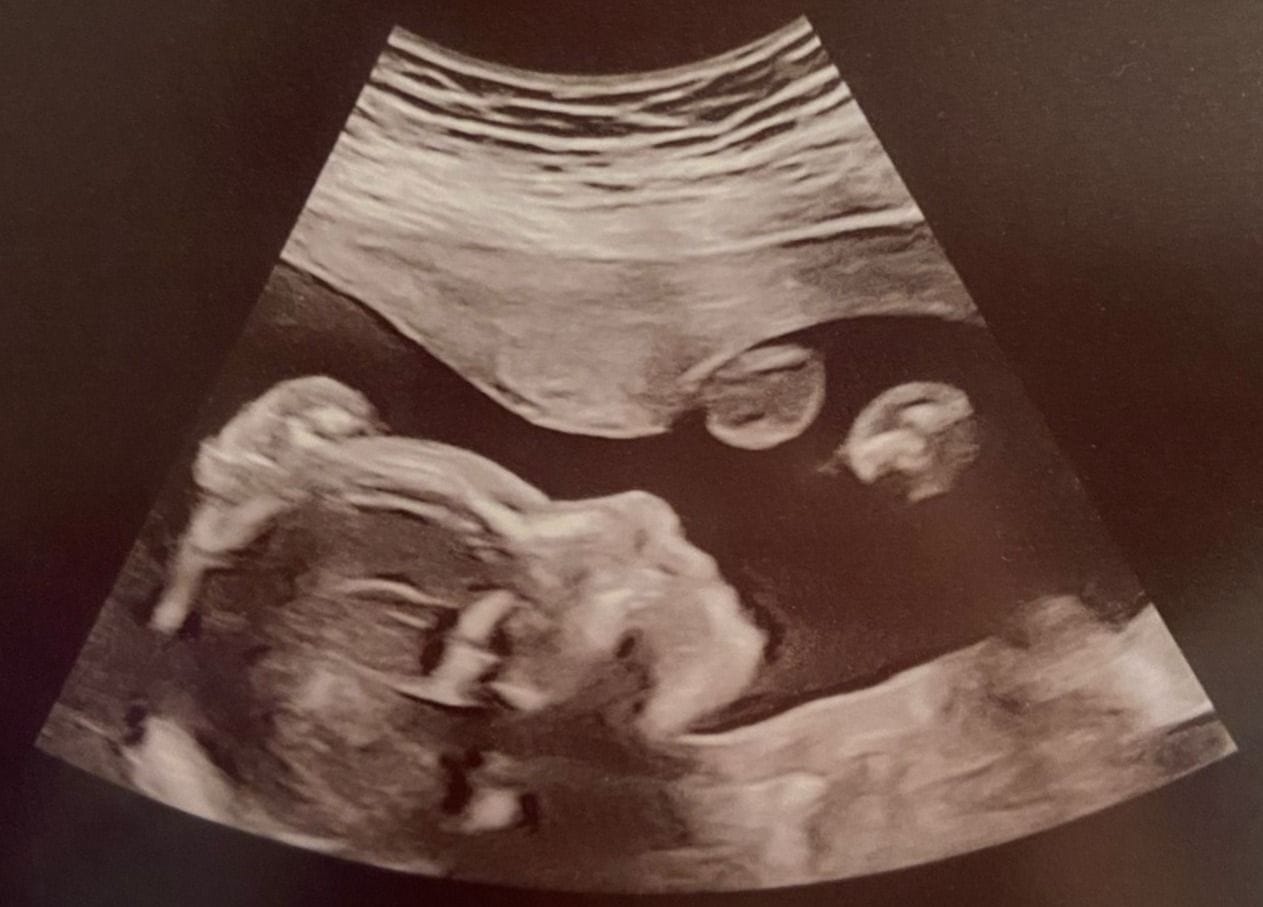

Source: Skyler Espinoza